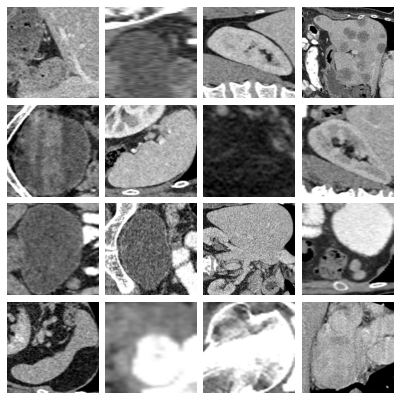

- organs_axial, Axial Organ Slices:

-

Dataset of axial image slices of 11 different organs, extracted from the Liver Tumor Segmentation Benchmark (LiTS) dataset [bilic2023liver] and the corresponding organ bounding box annotations from [xu2019efficient]. We derived a multi-class organ classification task with 11 labels by extracting a cropped image of each individual organ in each of the CT volumes using the bounding box annotations. We obtained a total of 1,645 organ images images. We removed 106 images for which the voxel size information was missing. The axes on one image were permuted to bring it to the same format as the other images. The images and masks were sliced from the original 3D volumes by taking the center of the organ bounding box in the axial plane. The Hounsfield-Units of the images were transformed into grayscale images by applying a window with a width of 400 and a level of 50, which are typical values for abdominal CT imaging. The images and masks were cropped to a square size in the physical space, by centering at the center of the bounding box and expanding the smaller side. The resulting images and masks were resized to pixels using bi-cubic and nearest neighbor interpolation, respectively. For visualization purposes, we additionally provide images averaged over the 10% central slices with the projected bounding boxes of all organs extracted from the image drawn on top.

- organs_coronal, Coronal Organ Slices:

Dataset of coronal image slices of 11 different organs, extracted from the LiTS dataset. The images were processed the same as described for the Axial Organ Slices dataset, except that the coronal projections were used.

- organs_sagittal, Sagittal Organ Slices:

Dataset of sagittal image slices of 11 different organs, extracted from the LiTS dataset. The images were processed the same as described for the Axial Organ Slices dataset, except that the sagittal projections were used.